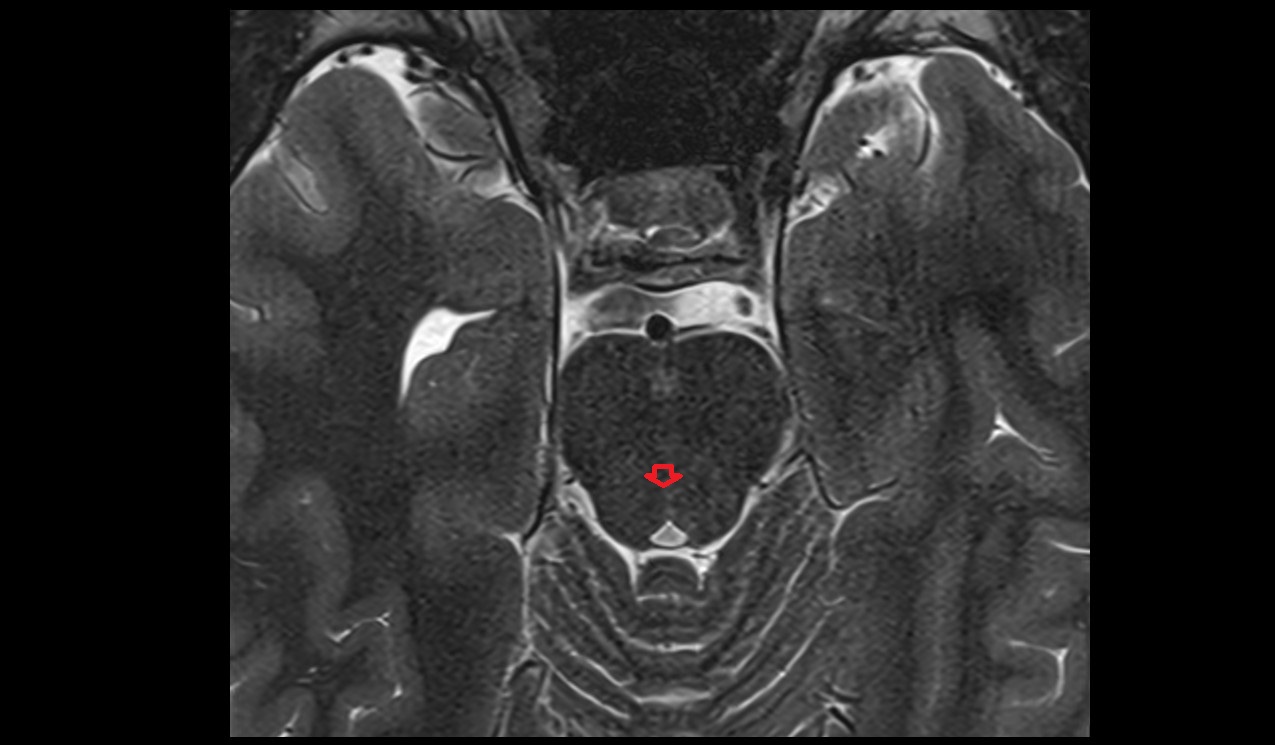

- Peripheral zone of prostate

- Anterior Fibromuscular Stroma of prostate

- Central zone of prostate

- Transitional zone of prostate